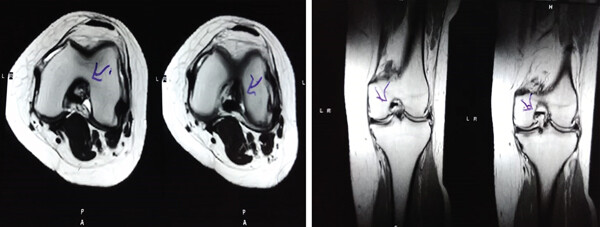

MRI檢查發現半月板損傷處修復:3D MRI 顯示 2 年時半月板撕裂難以辨別。

結論:滑膜間充質干細胞移植后,2年的隨訪中,患者的關節功能改善,MRI檢查發現半月板損傷處恢復,沒有發生導致研究終止的重大不良事件。可以達到干細胞治療半月板損傷長期療效的目標。

影像學檢查:4例MM皮瓣撕裂患者在治療前后交界區中央區域出現缺損,但其中2例患者該區域完全恢復穩定光滑狀態,另2例患者該區域部分恢復。治療前后交界區中央區域皮瓣撕裂的關節鏡評分為0.3±0.5,治療后為4.3±2.1,治療后評分顯著升高。2例患者原有放射狀MM撕裂在治療一年后愈合。

關節功能:治療后4周和52周的Lysholm評分顯著高于治療前。

結論:間充質干細胞移植后,隨訪24個月內,患者影像學和關節功能顯著改善,未發生嚴重不良事件。可以達到干細胞治療半月板損傷長期療效的目標。